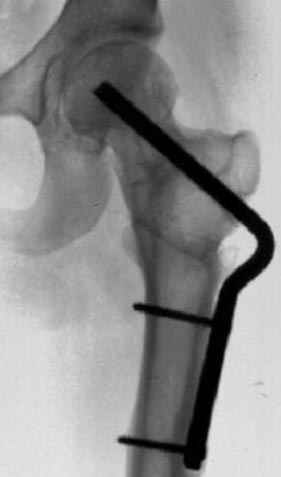

Несколько снимков из моей коллекции, чтобы разьяснить, почему мы до сих пор делаем различные варианты остеотомии.

На рисунке N1 предоперационный план лечения ложного сустава шейки бедра- линия ложного сустава, угол и направление введения импланта, клиновидная остеотомия в градусах и миллиметрах, второй снимок после коррекции, расчет, на сколько удлиняется конечность и размеры импланта;

N3 рисунок окончательный снимок, после операции моя рентгенограмма должен выглядеть примерно как эта картина. На N4 снимке клин перед удалением; N5 послеоперации 3 нед.; N6 окончательная рентгенограмма.

(доложен в Ст. Петербурге 2003 и в Москве 2004)

варус при проксимальном отделе 95 градусной пластиной.